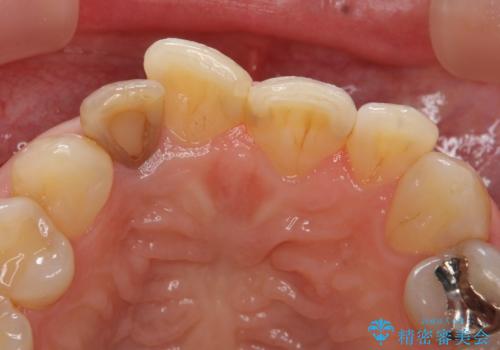

- 右上2番目の歯の変色が気になるといらっしゃった方の症例です。

再根管治療終了後、オールセラミッククラウンによる補綴を行いました。

今回用いたオールセラミッククラウンはジルコニアフレームという白い素材の上にセラミックを盛っているため、審美性が非常に高いのが特徴です。

また、ジルコニアは人工ダイヤモンドの材料にも使われているほど高い強度を持っており、そのためオールセラミッククラウンは審美性だけでなく、奥歯やブリッジの補綴も可能とするクラウンです。